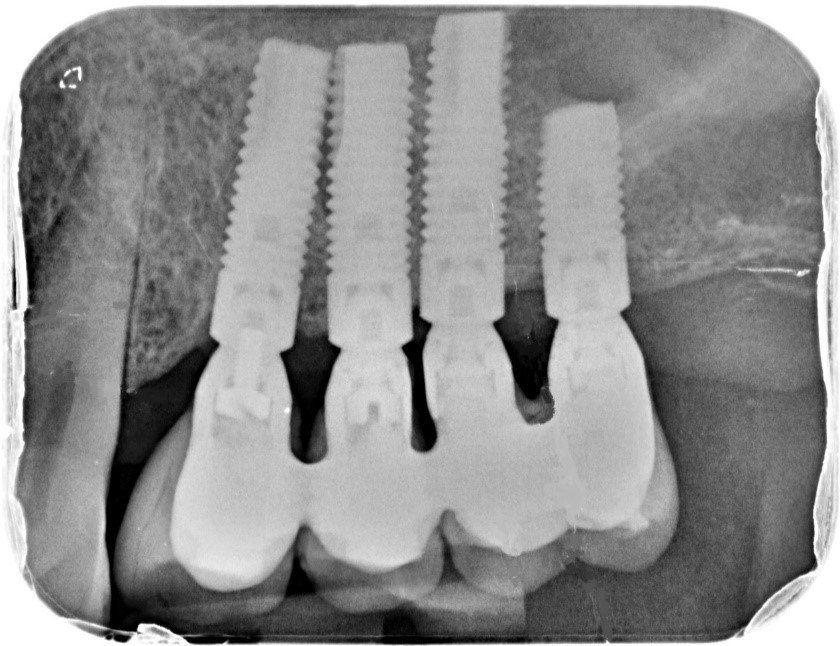

Dopo sei mesi dall’innesto vengono inseriti gli impianti e dopo ulteriori sei mesi vengono applicati i denti in ceramica.

Circa dieci anni fa il mio gruppo di lavoro ha pubblicato i risultati relativi a quindici pazienti trattati con la tecnica di Lundgren per un totale di 28 impianti seguiti per oltre un anno dopo l’applicazione dei denti. Non fu registrato nessun fallimento. Tutti gli impianti si rivelarono perfettamente integrati dopo un anno di carico e circondati da un notevole volume di osso neoformato. (14)

Un controllo sui medesimi pazienti a distanza di cinque anni ha confermato il mantenimento dell’integrazione ossea in tutti gli impianti, senza nessun fallimento. Al contrario si è rilevato un ulteriore crescita ossea attorno agli impianti. (dati non pubblicati)

Impianti multipli

Cinque anni dopo gli stessi pazienti sono stati nuovamente valutati clinicamente e radiograficamente. Tutti gli impianti risultarono stabili ed asintomatici. La perdita di osso marginale che ad un anno si era rivelata di una media di 0,36mm, dopo cinque anni si è dimostrata essere di 0,7 mm ovvero inferiori ai valori di riassorbimento consentiti di 0,2 mm per ogni anno di carico.